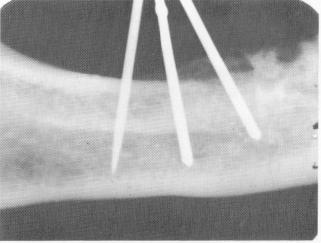

Fig. 14-25. The dried specimen was radiographed and the x-ray shows the pins to be buried in bone. The true situation was camouflaged by the buccal and lingual plates of cortical bone.

Formerly, when patients complained of pain or mobility, the implantologist could find little reason for it on x-ray studies. The following studies show that diagnosis solely by x-ray can be misleading. Linkow demonstrated experimentally with mandibular and maxillary jaws that the density of the buccal, lingual, or palatal cortical plates of bone can disguise the true resorption picture taking place in alveolar bone flanking a narrow pin. Scooping out alveolar bone, he placed the pins inside the hole (Fig. 14-24). Then he x-rayed the dried specimen (Fig. 14-25). Because the cortical plates of bone camouflaged the lack of alveolar bone, bone appears to completely encapsulate the triplant. He then cut away portions of cortical plates (Fig. 14-26) and once again radiographed the area (Fig. 14-27). In this way he established the fallibility of x-rays in diagnosing bone resorption in triplants.